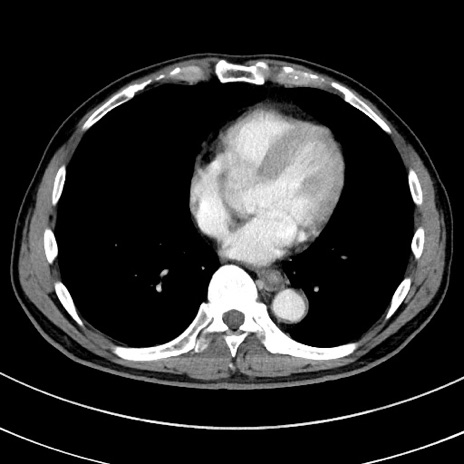

症例8(横断像)

【症例】 60歳代男性

【主訴】 黒色吐物

【現病歴】 4日前から嘔気自覚、2日前の朝食後にも嘔気あり、自分で手で嘔吐反射起こし嘔吐したところ血が混ざっていたため受診。

【既往歴】 5年前汎発性腹膜炎を伴う急性虫垂炎で手術、高血圧、前立腺肥大症、高脂血症

【身体所見】 腹部正中に手術癩痕あり 腹部平坦・軟圧痛なし膨満感あり

【データ】WBC 8400、CRP 4.54